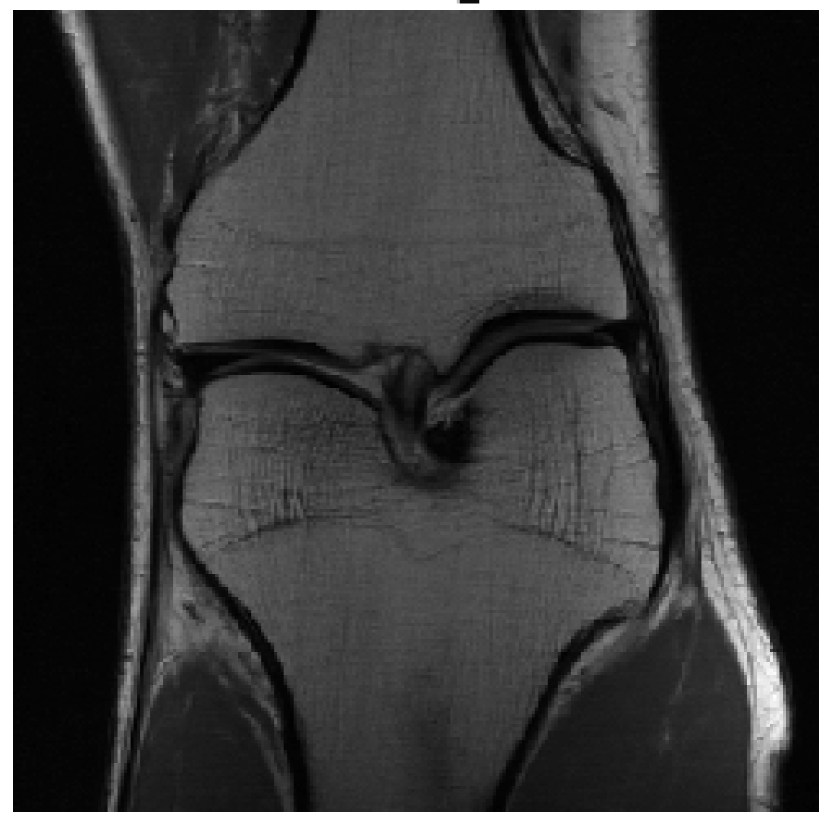

We evaluated our models on three data sets: the validation set as in Zbontar et al. (2018), and the test and challenge sets through the fastMRI website. A summary of these evaluations can be found in table 1111Results on the challenge data set will be added once publicly available.. To assess image quality more closely, we show some exemplary reconstructions from each model in figure 1.

Reconstruction

Reconstruction

Ground Truth

Reconstruction

Reconstruction